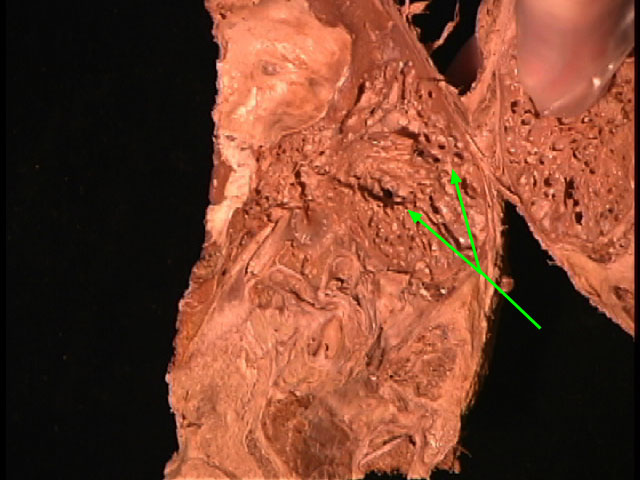

Facial canal

Stapes

Internal Acoustic Meatus

Vestibular (Oval) Window

Geniculate Ganglion

Inferior Tympanic Canaliculus

Cochlea

Incus

Epitympanic Recess

Mastoid Air Cells

Malleus

Tympanic Membrane

Tegmen Tympani

Stapedius m.

External Acoustic Meatus

Auditory Tube

Tensor Tympani m.

Promontory

Vestibulocholear n.

Semicirular Canals

Facial n.

Petrotympanic Fissure

Cochlear (Round) Window

Chorda Tympani

Greater Petrosal n.

Lesser Petrosal n.